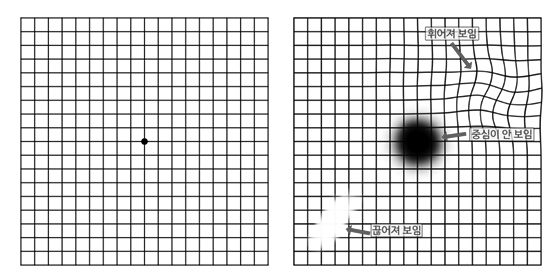

사물이 찌그러져 보이는 변시증이나 시야의 중심 부분이 까맣게 보이는 중심암점 등의 자각 증상이 있으면 안과에 오셔서 검진을 받아주셔야 합니다.

황반변성 자가 검진

자가 검진 방법

안경을 착용하시는 분은 안경을 써주시고, 돋보기(근용안경)을 착용하시는 분은 착용해주세요.

30cm~40cm 거리에서 검사를 시작합니다.

한쪽 눈을 가리신 상태에서 격자 중앙에 있는 점이 보이시는지 확인해주세요.

중앙의 점을 보면서 동시에 네 개의 모서리가 보이시는지 확인해주세요.

자가 검진 확인 방법

- 1. 중앙의 점이 보이셔야 정상입니다.

- 2. 선들을 봤을 때 휘어지지 않고 곧게 보여야 정상입니다.

- 3. 선들을 봤을 때 끊어진 것처럼 보이거나, 희미하거나 안 보이는 부분이 없으셔야 정상입니다.

- 4. 네 개의 모서리가 다 보여야 정상입니다.

(이 중 하나라도 다르게 보이시면 즉시 안과에서 정확한 검사를 통해 확인해주셔야 합니다.)

* 이 자각 검사는 안과 검진을 대체할 수 없습니다. 정확한 진단을 위해서는 반드시 안과에서 검사를 받으셔야 합니다.

위의 그림처럼 보이는 부분이 있으면 반드시 안과에 방문하셔서 정확한 진단을 받아주셔야 합니다.